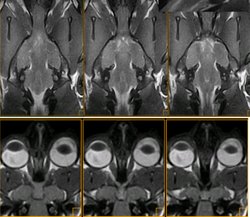

Detalle del quisma óptico de un gato (imagen de resonancia magnética)

Vía óptica. Cocker. Nervio óptico (n), quiasma óptico (o) Se muestran 4 secuencias de resonancia magnética, en positivo (las de arriba) y en negativo (las de abajo) A: SE T2 dorsal. B: SE T1 transversal. C: SE T1 sagital. D: SE T1 oblícuo, siguiendo la trayectoria del nervio óptico izquierdo, del cual se visualiza perfectamente su entrada por el agujero óptico del esfenoides.